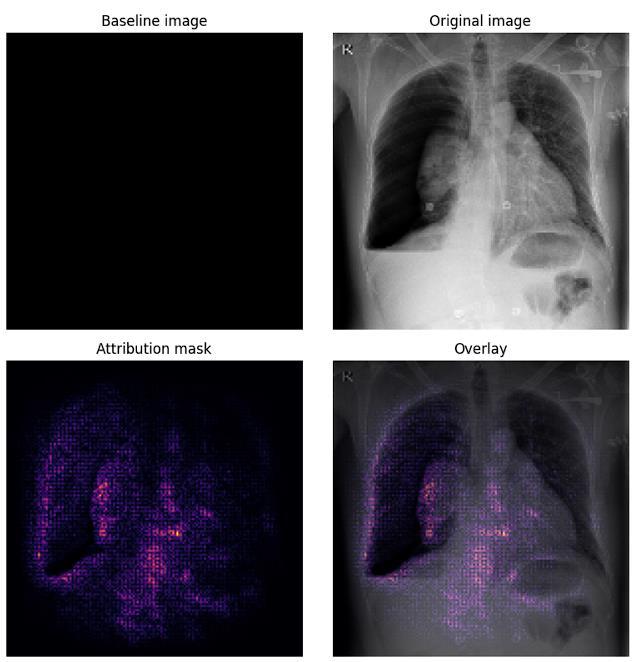

ImageOutputwithDiseaseClassificationandImageSegmentation

To provide visual interpretability of the model's predictions, integrated gradients are calculated for the input image. Integratedgradientshighlighttheimportantpixelsthat contributetothemodel'sdecision,whichhelpsinunderstandingthe model's focus areas. The integrated gradients are normalized and visualized alongside the original image, showing how different parts of the X-ray contributed to the classification made by EfficientNet-B2 and Inception V3. This step enhances transparencyandtrustinthedeeplearningmodel'sdecision-makingprocess.